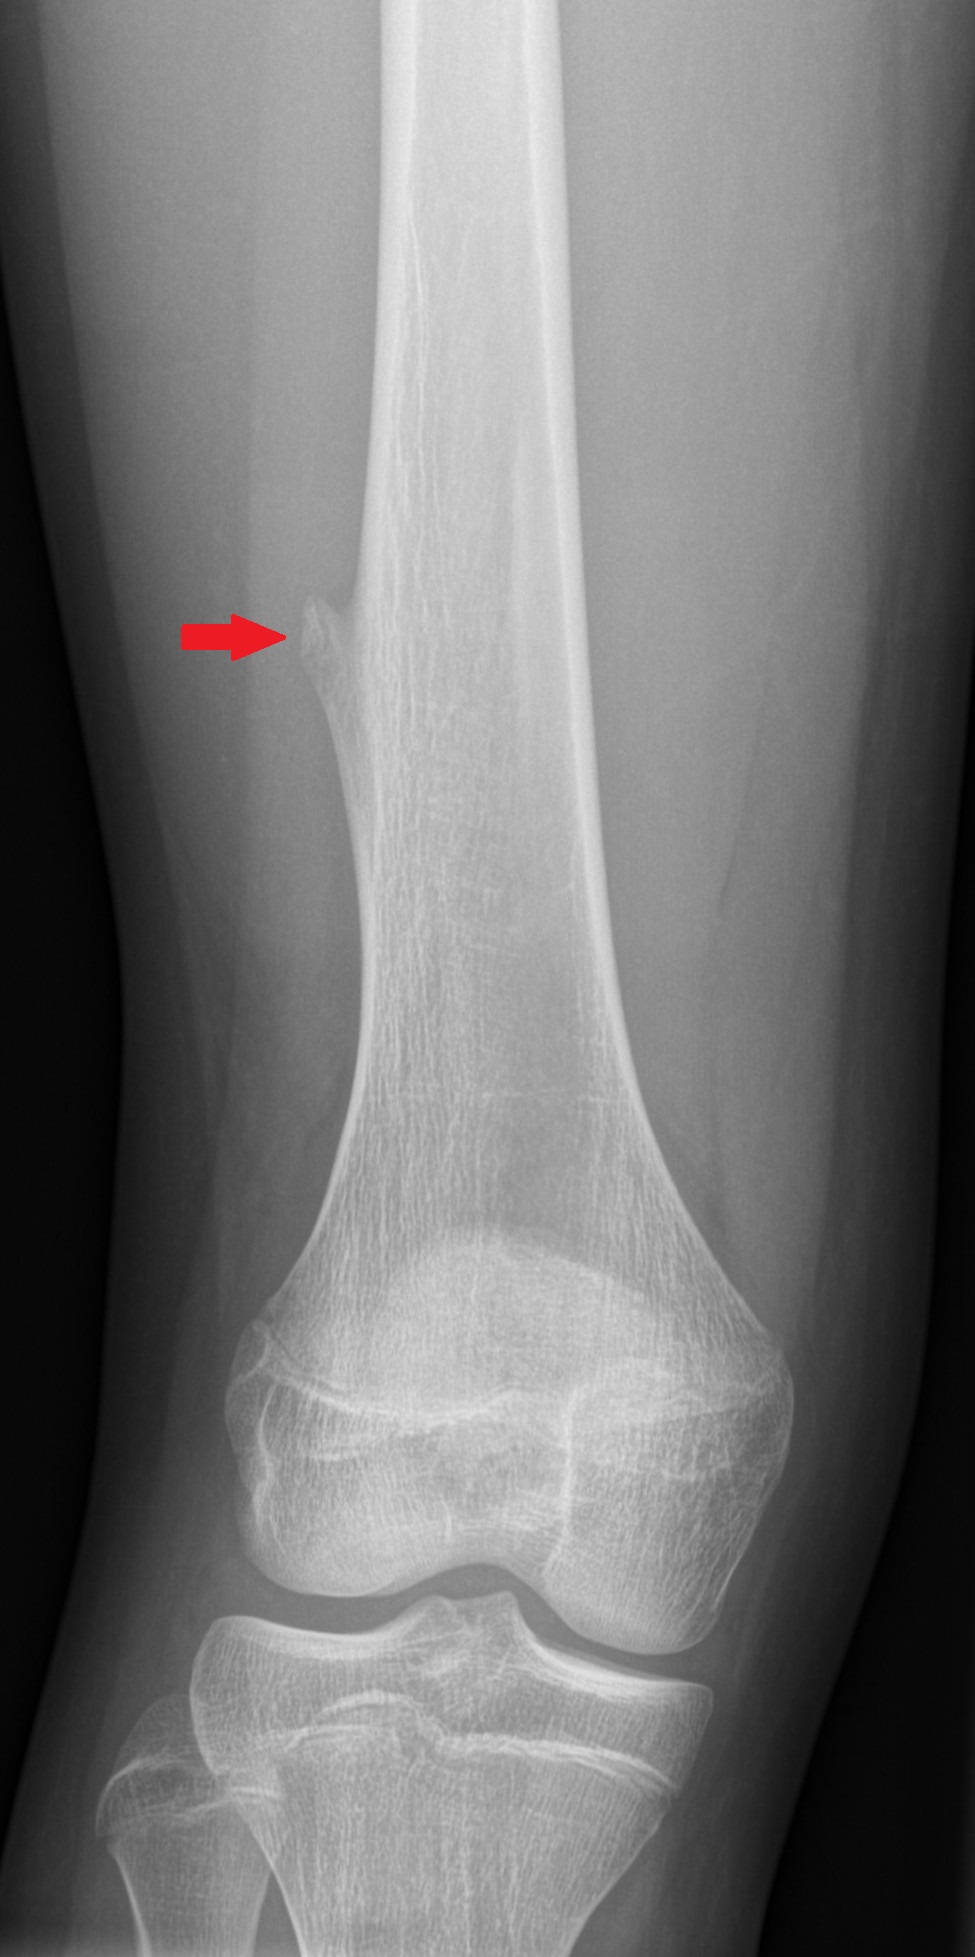

Lasten ja nuorten ortopedia tutkii ja hoitaa kasvuikäisten tuki- ja liikuntaelinten sairauksia ja vammoja sekä niiden jälkitiloja.